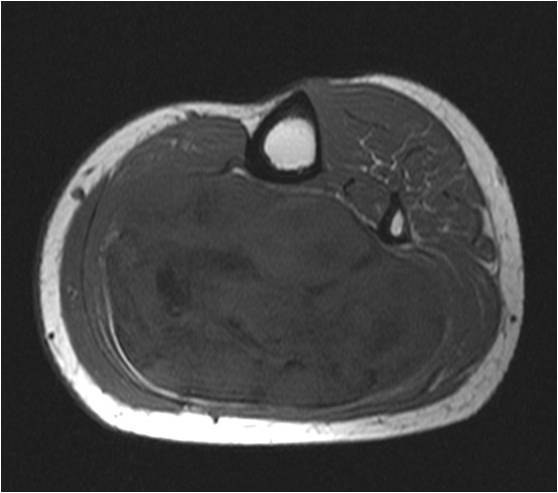

On radiographs, Low Grade Fibromyxoid Sarcoma presents as a discrete mass with soft tissue density without mineralization. MRI shows a well circumscribed heterogeneous mass, primarily hypo or isointense to muscles on T1-weighted image. The majority of tumors demonstrate heterogeneous signal intensity on T2-weighted images, correlating with the histological characteristics of low grade fibromyxoid sarcoma. Although 48 % of the patients demonstrate hyperintense signal and the rest of patients present admixed of hypo and Isointense signals (Fig. 1-5).

Fig. 1 & 2: MRI Axial (Fig. 1) and Coronal T1-weighted MR image (A) of a Low Grade Fibromyxoid Sarcoma demonstrates a well-defined mass of intermediate signal intensity with muscle and central areas of hypo intensity in the posterior compartment of the calf.